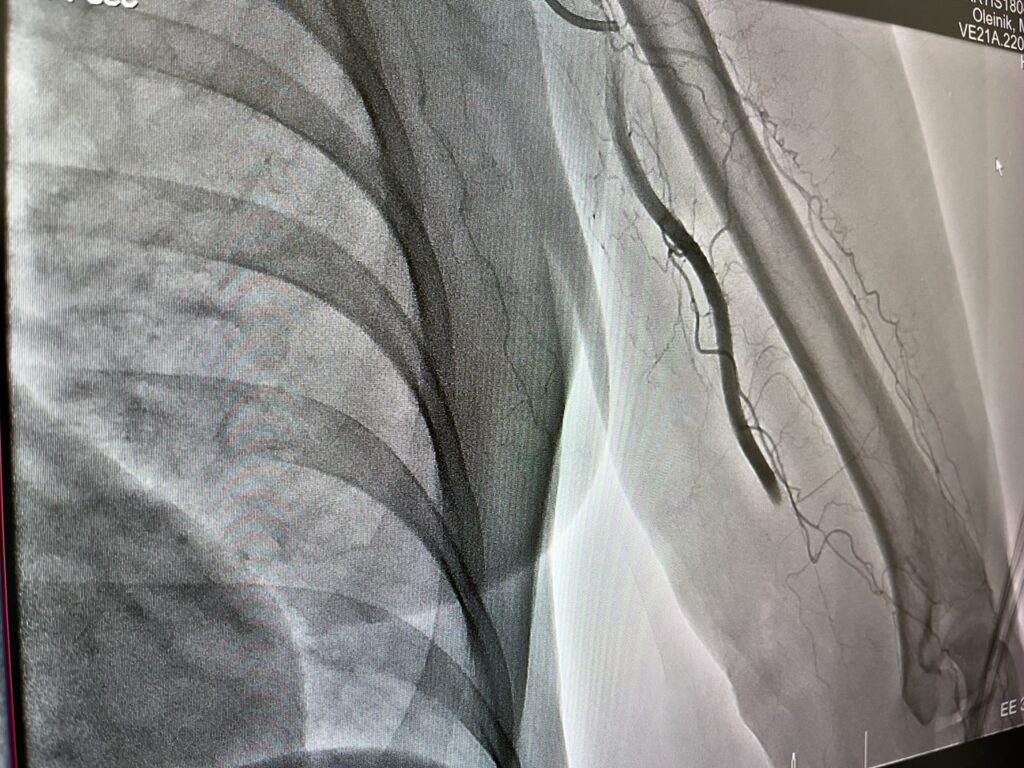

«Пациентке провели процедуру тромбэкстракции – через бедренную артерию микрокатетером специалисты достигли места закупорки сосуда и устранили тромб», — рассказал в своем телеграм-канале министр здравоохранения Кузбасса Андрей Тарасов.